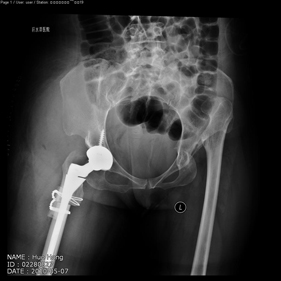

shortening osteotomy and total hip replacement for bilateral severe dysplasia of hip with high riding